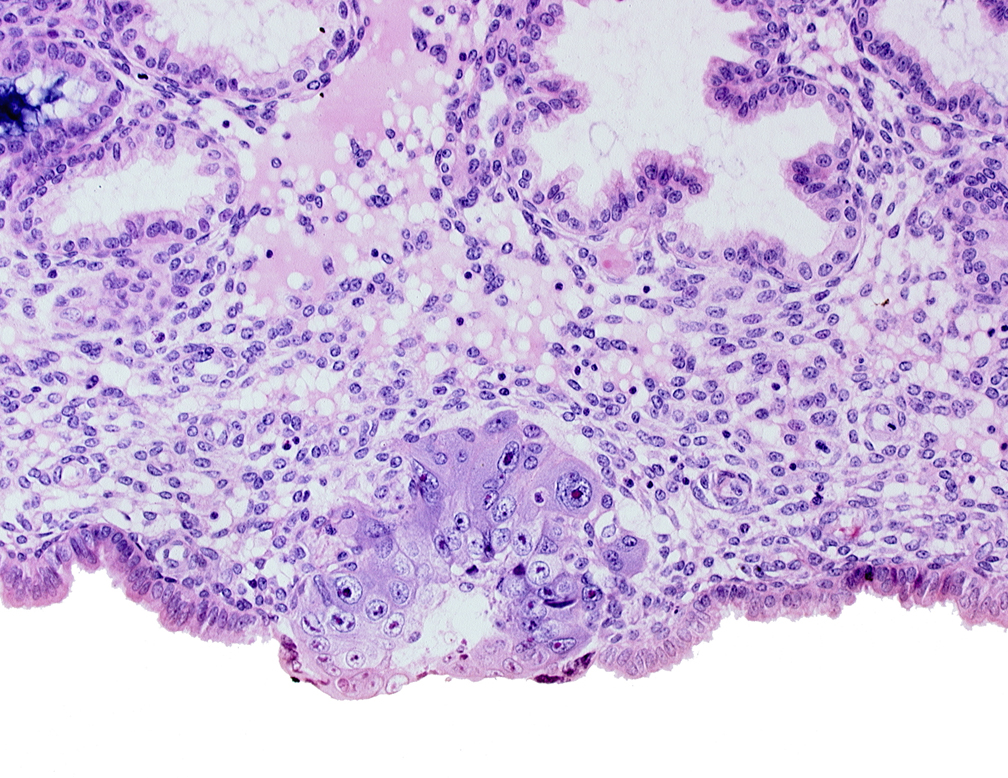

blastocystic cavity (blastocoele), cytotrophoblast, edge of membranous trophoblast at abembryonic pole, solid syncytiotrophoblast

Keywords: blastocystic cavity (blastocoele), cytotrophoblast, edge of membranous trophoblast at abembryonic pole, solid syncytiotrophoblast